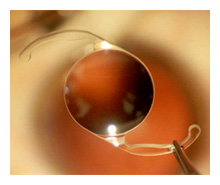

AcrySof IQ lens implant inside the eye.

This eye is "dilated" (pupil is enlarged)

- otherwise you would

not see the lens.